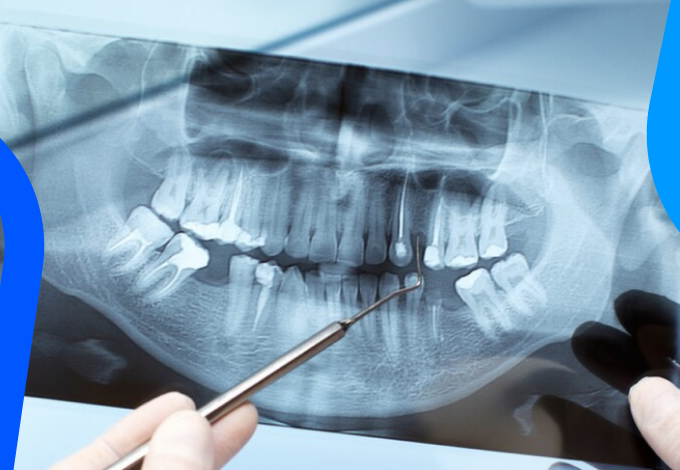

- Prova Radiográfica

- Apenas após as etapas prévias é que uma radiografia periapical deverá ser realizada;

- Avalia-se o comprimento atingido e só assim é possível partir para a etapa obturadora;

- Importante salientar que o uso do localizador apical é recomendado e, em casos específicos, pode haver uma discreta mudança de local entre a saída foraminal e o vértice da raiz.

- Radiografia final: É de extrema importância conferir a qualidade da obturação.

- Radiografia da qualidade da obturação;

- Radiografia final.

- Radiografia comprobatória;

- Radiografia periapical;